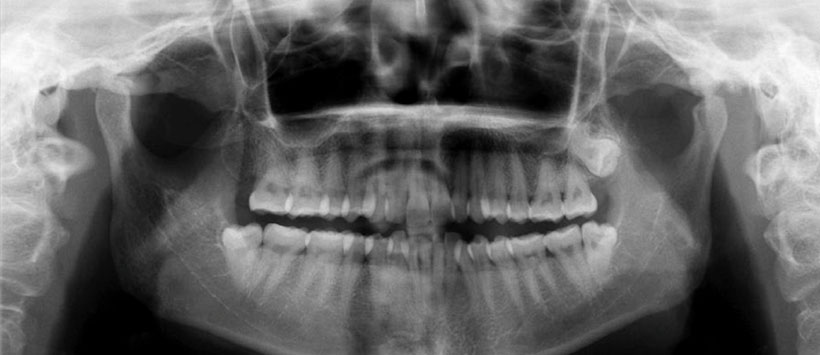

Caso 1: Mujer de 60 años fue remitida con motivo principal de incomodidad durante la masticación durante 3 años. El examen físico mostró asimetría facial y una ligera desviación de la línea media de la mandíbula hacia el lado izquierdo. También presentó sensibilidad en el área derecha de la ATM (Figura 1, 2 y 3).

Figura 1: Radiografía panorámica que muestra morfología asimétrica del cóndilo mandibular derecho con borde irregulares en zona posterior (flecha negra) y una pequeña imagen radiopaca de densidad cálcica en forma de masa (flecha blanca).